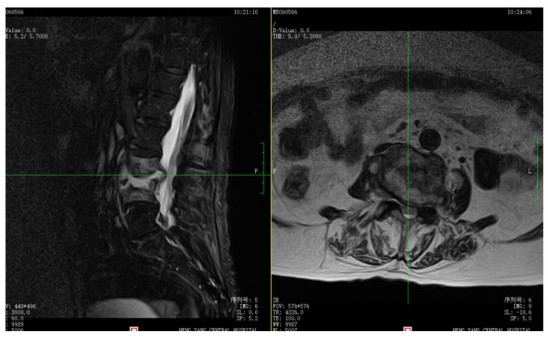

為解決老人病痛,脊柱外科錢軍博士團隊對其進行了詳細(xì)的查體以及全面細(xì)致的評估,診斷為L3、4脊柱結(jié)核伴病理性骨折、椎旁膿腫,患者腰部疼痛癥狀逐漸加重,病灶已經(jīng)壓迫神經(jīng)引起了截癱。